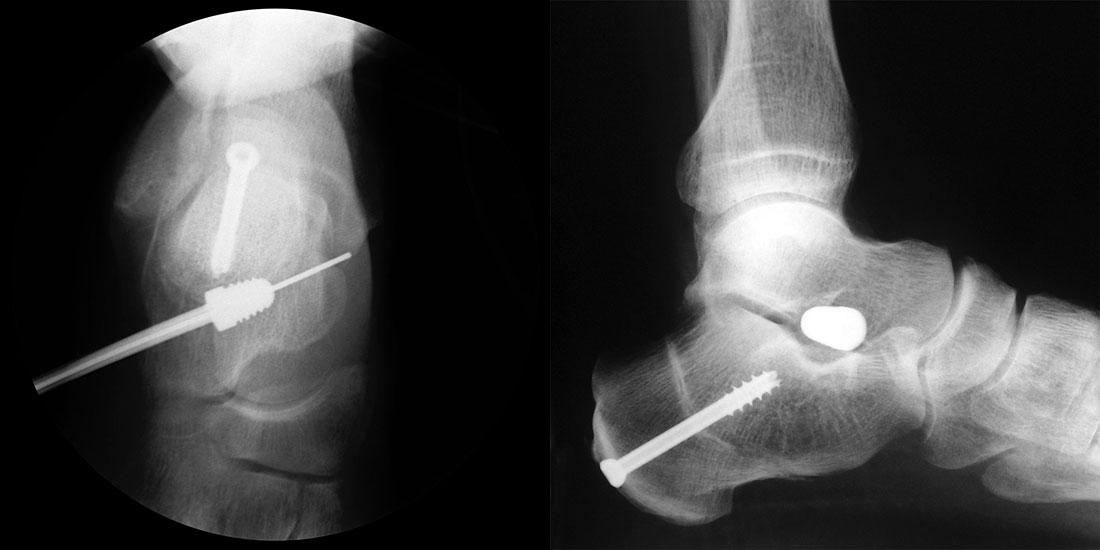

Bei Rückfussfehlstellungen ist meist eine knöcherne Korrektur des Kalkaneus indiziert. Dabei wird das Fersenbein im Bereich des Tuber calcanei durchtrennt und der Achillessehnenansatz nach medial oder lateral geschoben. Zusätzlich ist eine Rotation des Tuber möglich, wodurch sich der Korrektureffekt noch verstärkt. Durch die Wahl der Osteotomieebene kann die Verscheibung mit einer Verlängerung oder Verkürzung des Fersenbeins kombiniert werden. Die Osteosynthese erfolgt typischerweise durch perkutan eingebrachte Schrauben.

Durch eine V-förmige Schnittführung kann eine Translation des Tuber calcanei nach dorsal zuverlässig verhindert werden, bei hoher primärer Stabilität.

Kanülierte Schrauben bis 80 mm Länge.

Kirschnerdraht mit 2,0 mm zur Verschiebung des Tuber calcanei.